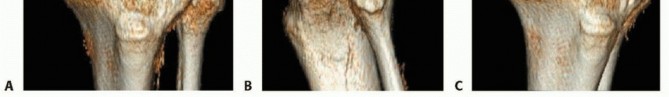

### FIG 9 • Critically ill elderly polytrauma Jehovah's witness patient with left C1 distal femur fracture. A,B. Initial injury AP and lateral views. C,D. Due to extremely low hematocrit, external fixation was the only surgical option allowed to minimize blood loss. Radiographs in bridging external fixation. The AP shows excellent alignment but the lateral shows the expected extension deformity secondary to pull of gastrocsoleus complex. E,F. After 5 weeks in an external fixator, AP and lateral radiographs show callus formation (red arrows). Patient is now cleared for definitive surgical intervention. Antegrade intramedullary nailing has been described and can be used for distal fractures with a large enough distal segment to allow for two locking screws. Malalignment has been a problem, as has adequate fixation. 4, 8 Retrograde intramedullary nailing can be used in the following cases ( FIG 10): All extra-articular type A fractures greater than 4 cm from the joint. This minimal length of the distal femur allows for multiplanar interlocking in the distal fragment. Type C1 or C2 fractures where the articular fracture can be anatomically reduced closed or with limited exposure. Percutaneous screws are used for the articular injury. Periprosthetic fractures around a total knee arthroplasty with an “open box” femoral component Most surgeons prefer to use a long nail, but short supracondylar nails are available as well. Multiple-hole short supracondylar nails have fallen out of favor. Plate fixation ORIF with plates can be used for all types A and C fractures but is ideal for the following injuries: Very distal type A fractures within 4 cm of the knee joint All articular type C fractures, but always for C3 types Periprosthetic fractures about a “closed box” femoral component of a total knee arthroplasty The partial articular type B1 or B2 if an antiglide plate is needed Plate options (preferred to least preferred; fixed-angle devices preferred) Fixed-angle locking plates (percutaneous jigs are advantageous and allow for minimally invasive techniques) Variable-angle (polyaxial) locking plates—allow for “fixed variable locking” within a defined range. It is useful for distal fractures and allows for increased screw 473 trajectories to gain additional locked fixation in short segments, which may not be feasible with fixed-angle trajectory plates ( FIG 11).

### FIG 10 • A,B. AP and lateral radiographs of an elderly patient with multiple comorbidities with an extra-articular distal femur fracture (AO type A; an incomplete intercondylar split— red dashed arrow). C,D. Postoperative radiographs showing stabilization with retrograde intramedullary nail. E,F. One-year postoperative radiographs showing a healed fracture with some subsidence of the metaphyseal region and mild protrusion of hardware through the notch. Ninety-five-degree condylar screw Ninety-five-degree blade plate Nonlocking plates with or without medial support (medial plate or external fixation) Limited internal fixation Limited fixation with screws only can be used for partial articular type B, especially type B3. The amount of open reduction required depends on the adequacy of closed reduction techniques and obtaining an anatomic reduction of the joint surface. Headless screws are useful for type B3 fractures in which the screws have to penetrate the joint surface ( FIG 12). Countersinking the screw heads can also be performed. Biomechanics of fixation: implant considerations There has been concern that the newer locking plate constructs are too stiff, resulting in inconsistent and asymmetric callus formation. 9 Some clinical evidence show less callus formation with stainless steel plates versus titanium plates. 9 Conversely, a biomechanical study has not shown a significant difference mechanically between constructs of stainless steel LISS plates with bicortical screws or titanium LISS plate with unicortical screws.1 474